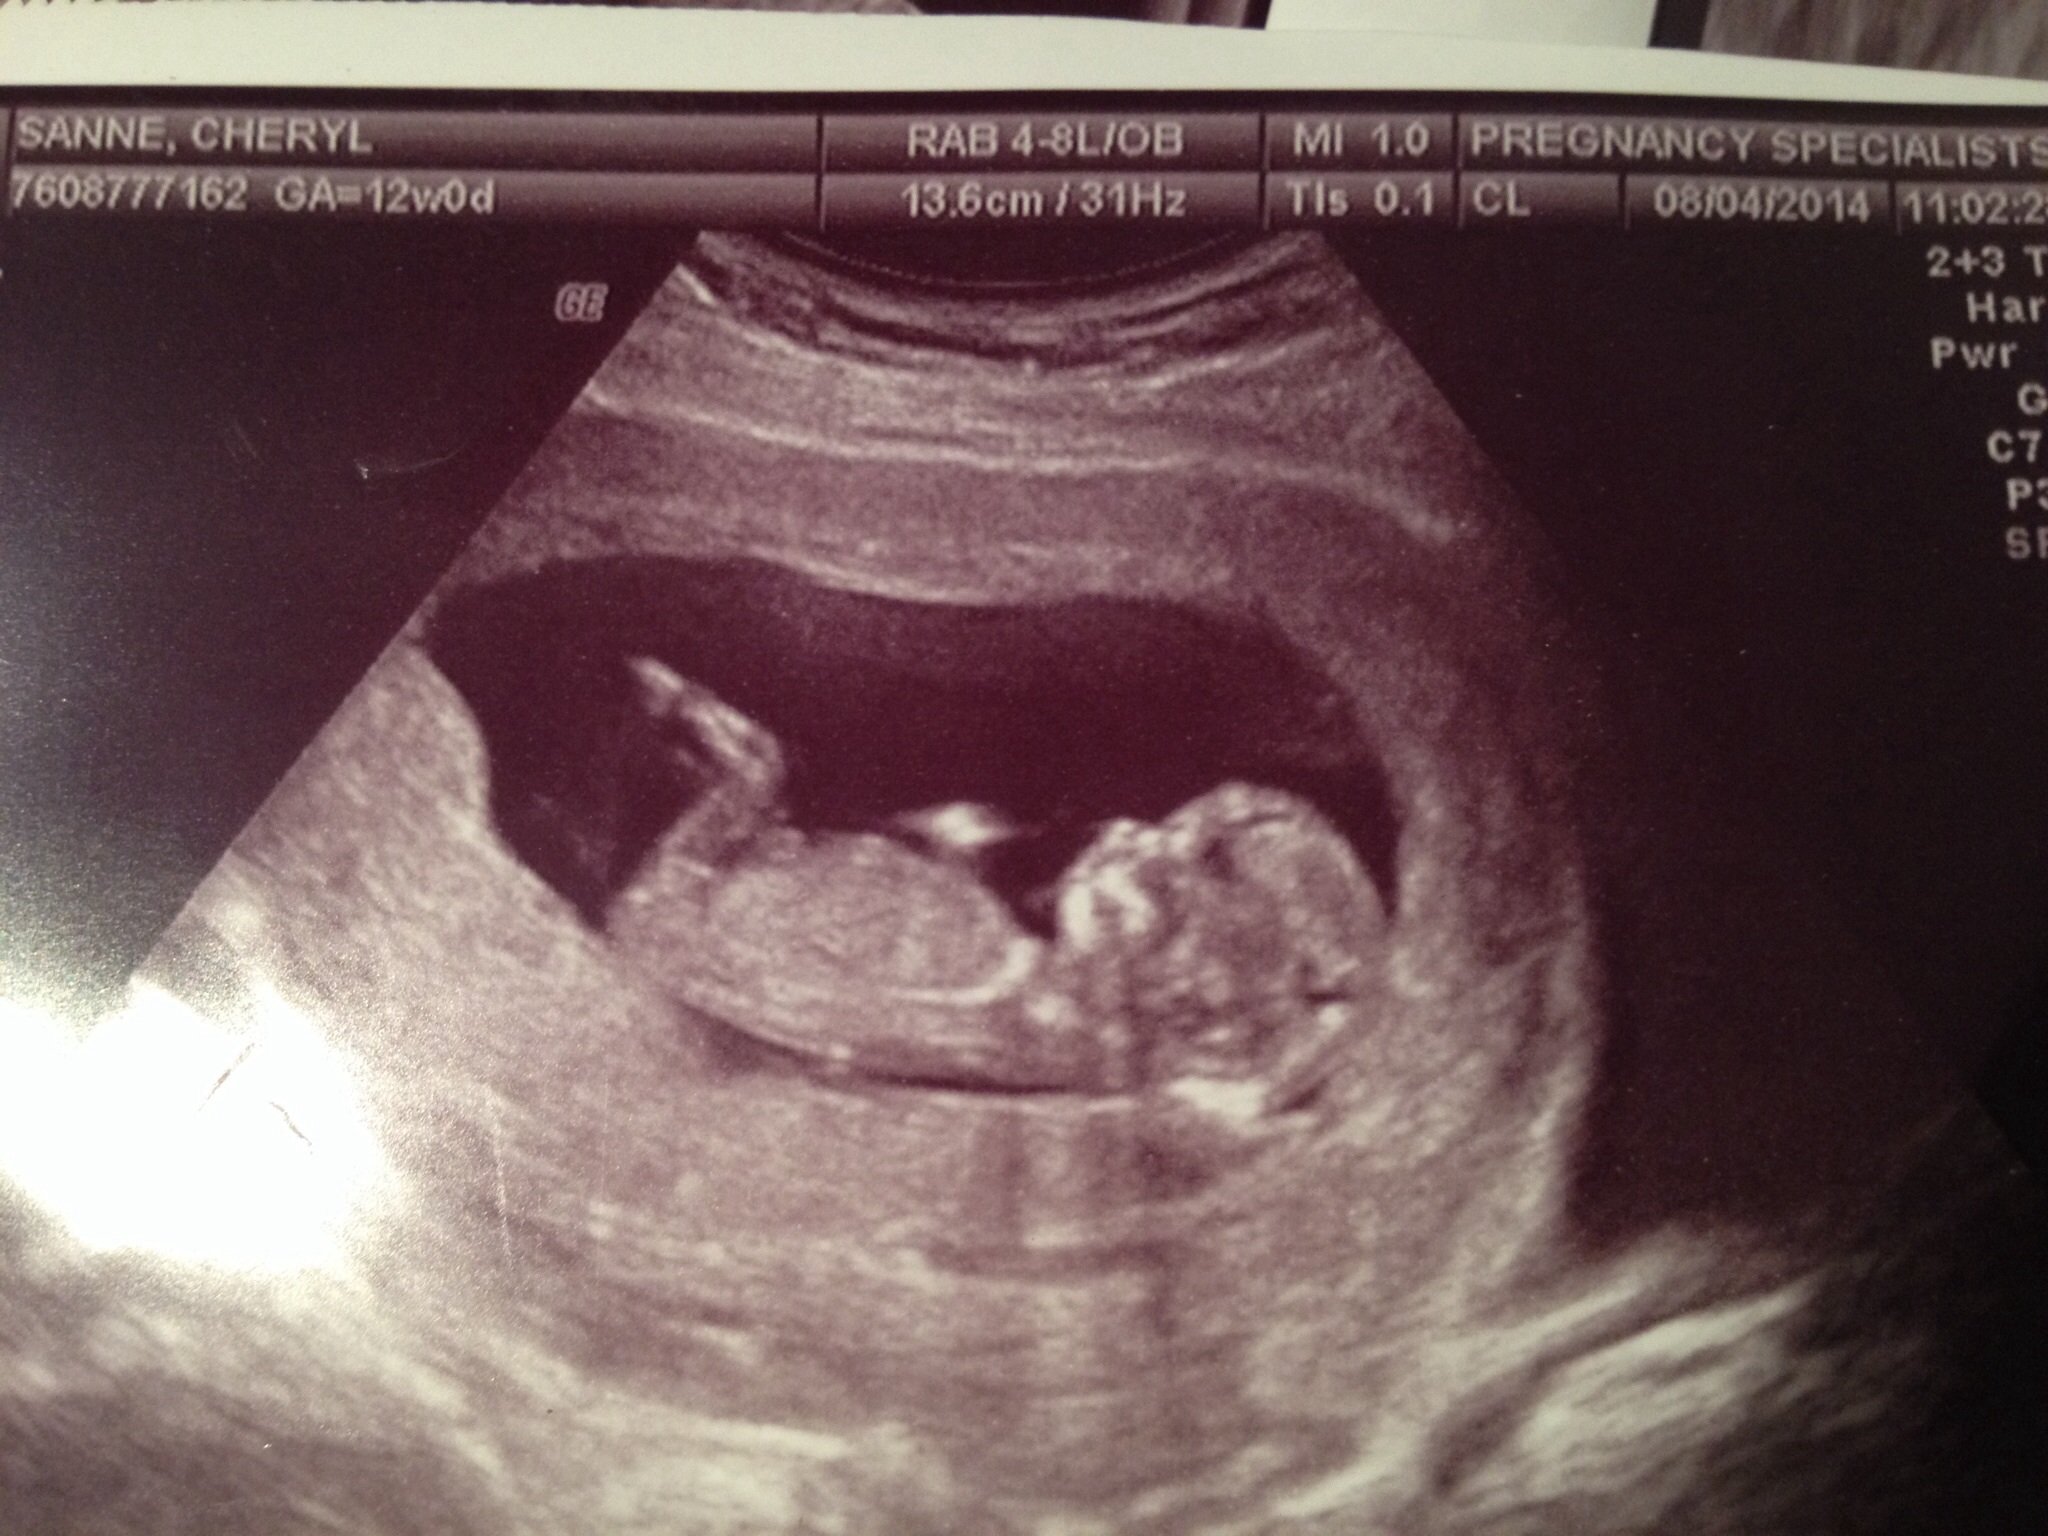

Ultrasound: Healthy singleton pregnancy. Heart rate 155, good movement. My placenta is located in the front (anterior), which surprised me. I guess it might be longer for me to feel the baby kick, but that's OK. NT measurement was 1.5 mm. Baby dated 12 w 5 d by CRL and 12 w 2 d by LMP, so we are more or less on target.

Blood test: After my blood tests were done, my risk for downs or trisomies was calculated to be less than 1 in 10,000. I'm very happy with these numbers!